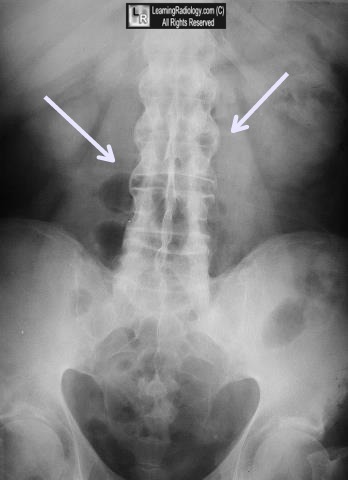

www.researchgate.netBamboo Sign - Ankylosing Spondylitis - RadRounds Radiology Network

radrounds.combamboo ankylosing spondylitis radrounds

Bamboo Spine Is A… - Radiology Matrix - Medical Education | Facebook

ne-np.facebook.comBamboo Sign | Ankylosing Spondylitis, Radiology, Samsung Galaxy Phone

Bamboo Spine (ankylosing Spondylitis) | Radiology Reference Article